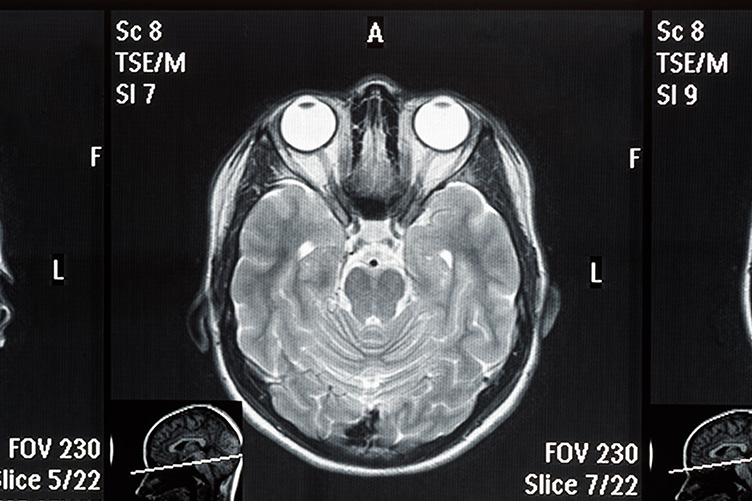

Vor der Behandlung wird eine individuelle weiche Netzmaske angepasst. Diese stabilisiert den Kopf. CT- und MRT-Bilddaten definieren die genaue Größe und Lage des Tumors. Strahlen werden dadurch punktgenau eingesetzt.

Die Cyberknife® Technologie ermöglicht, sowohl gut- als auch bösartige, wiederkehrende Hirntumoren und Metastasen zu behandeln. Umliegendes Gewebe wird nicht beeinträchtigt. Modernste Technik kann das Wachstum schwer erreichbarer Tumoren gezielt stoppen.